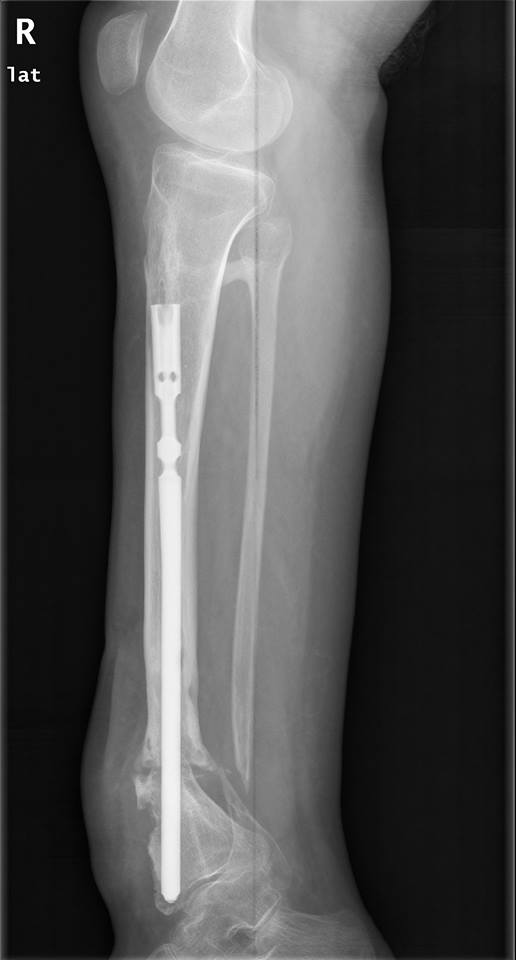

Уважаемые коллеги, Есть девушка с таким вот гвоздиком. В плане -

удаление и реостеосинтез.

Вопрос - как минимально инвазивно удалить это чудо? Понимаю, что ранее

вопрос поднимался, но тут, мне кажется, случай не стандартный. Спасибо.